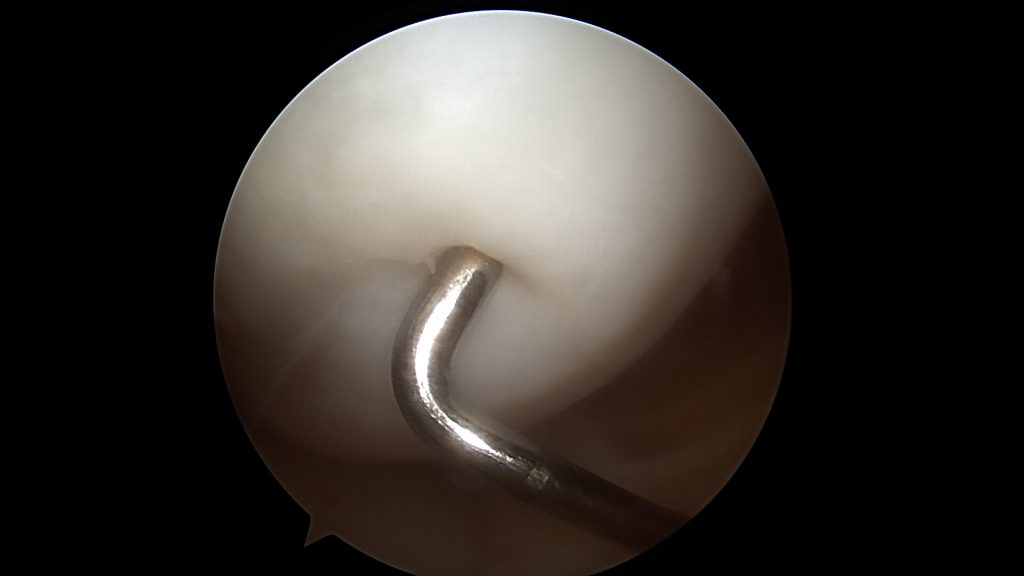

Powierzchnie uszkodzenia trzeciego stopnia wyrównuje się mechanicznie, aby rozpulchnione fragmenty chrząstki nie stanowiły powierzchni ciernej.

W przypadku niewielkich uszkodzeń czwartego stopnia, punktowych, poniżej 1 cm2, stosuje się odświeżenie dna ubytku. W ten sposób wydostająca się spod chrząstki krew tworzy skrzep wypełniający ubytek. Kiedy jednak jest on większy konieczne jest jego wypełnienie materiałem. Stosuje się preparaty hyaluronowe (np: Hyalofast) lub błony kolagenowe. Są one rusztowaniem dla komórek, które zagnieżdżają się w nich oraz rozpoczynają tworzenie regeneratu chrząstki stawowej.